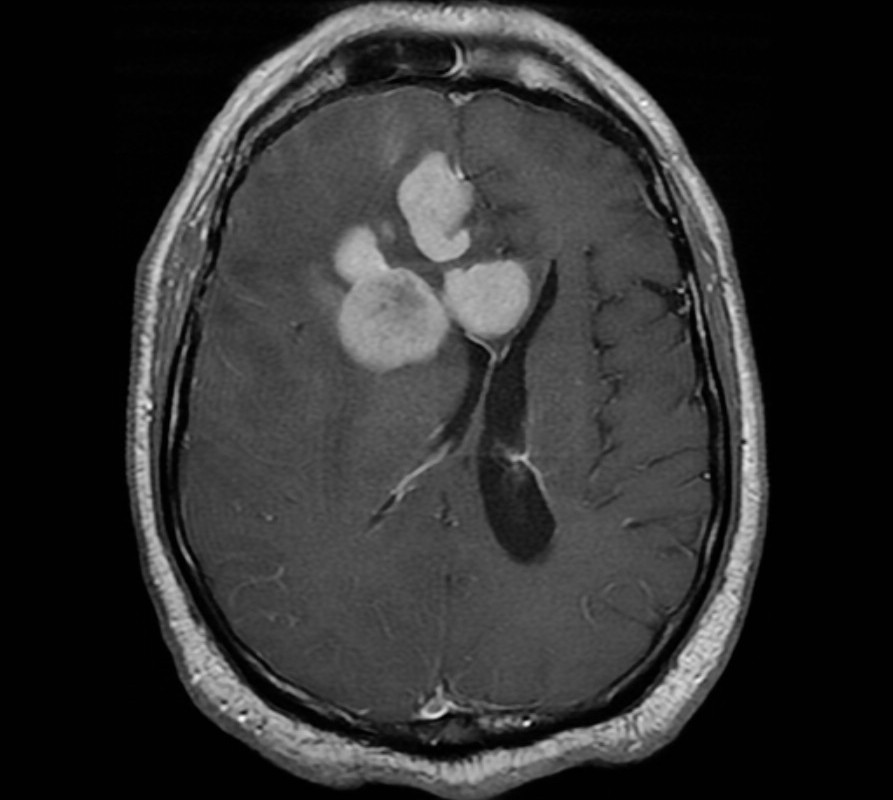

Η μαγνητική τομογραφία δείχνει, συνήθως, όγκους ομοιογενείς που ενισχύονται από το σκιαγραφικό μέσα στην περικοιλιακή εν τω βάθει λευκή ουσία. Οι όγκοι, συνήθως, είναι πολυεστιακοί. Και η ανομοιογενής ενίσχυση του σκιαγραφικού, δεν είναι ασυνήθης, ειδικά σε ασθενείς που έχουν καταστολή του ανοσοποιητικού τους συστήματος.